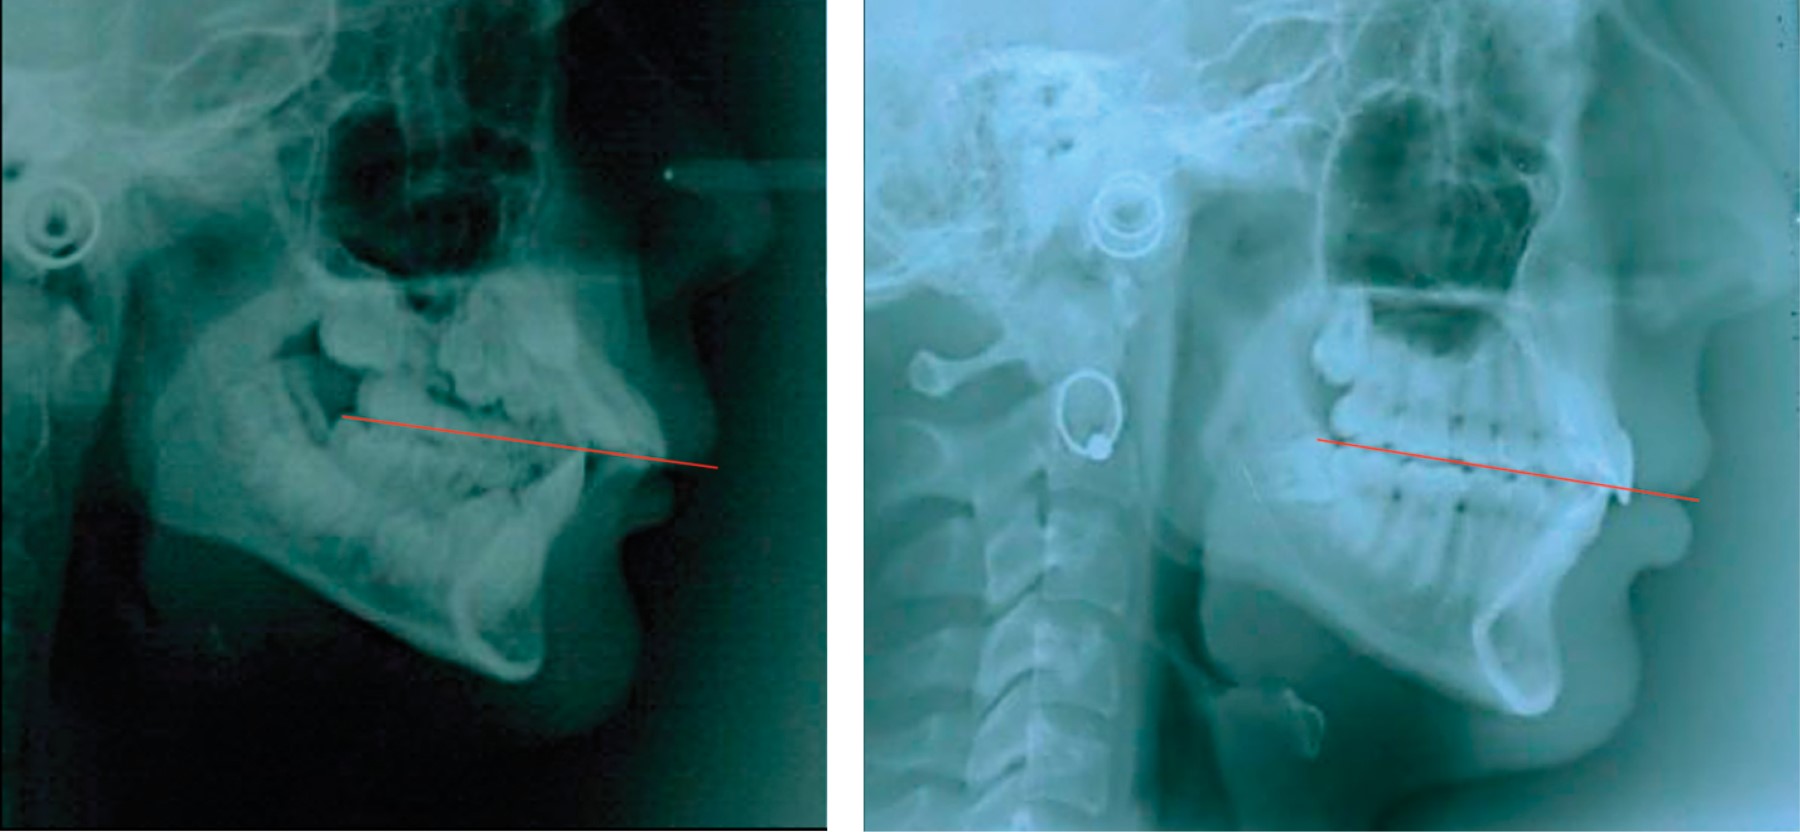

Conforme se va completando la dentición temporal se va produciendo el descenso del plano oclusal, que en el recién nacido está prácticamente a nivel de las ATM. En virtud de la dirección de los centros de crecimiento del maxilar superior, que es hacia abajo y adelante, se establece el primer plano oclusal, ya que a diferencia de la dentición permanente no presenta las características básicas para el diagnóstico tridimensional del plano oclusal (Figura 1) como la curva de Spee y/o de Wilson, donde se analizan las relaciones sagitales y transversales junto con la dimensión vertical.3,7,8

La curva de Spee se refiere a una curvatura sagital que va desde la cúspide de los caninos inferiores y se desplaza hacia atrás pasando por las cúspides de los premolares y molares; si la curvatura se continuara hacia atrás, pasaría a través del cóndilo (Figura 2).

La curva sagital del plano oclusal está diseñada para permitir la desoclusión de los dientes posteriores en el movimiento de protrusión y de esta manera se evitarán contactos prematuros de oclusión, en combinación con la guía anterior y guía condilar. Cuando se presenta la separación de los dientes posteriores por medio del contacto incisal, los músculos elevadores ejercen presión (de carga y no sobrecarga) sobre los dientes anteriores y cóndilos. Si no se llegara a cumplir con esta sincronía de movimiento y fuerza regulada por el sistema sensor, sin duda comenzará una serie de daños directamente sobre la masa dental, músculos, articulaciones y estructura periodontal.

Shudy puntualizó que la relación entre el crecimiento efectivo vertical condilar (crecimiento horizontal) y el crecimiento vertical de los molares determina si la mandíbula rota hacia abajo o hacia adelante, o simplemente no rota. El plano oclusal es el efecto, no la causa de la relación anatómica atribuible al crecimiento condilar (relacionado al crecimiento vertical) como la clave para los cambios del crecimiento vertical.15,16

Por lo general, las áreas de mayor fuerza oclusal y de mayor área de contacto oclusal es en el lado hacia donde se desvía la mandíbula y hacia donde está inclinado el plano oclusal. Cabe destacar que no necesariamente es el lado donde predomina la sintomatología de las articulaciones (Figuras 4 y 5).11,12,18,19,21